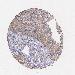

UROTHELIAL CANCER - Protein expressioni

A mouse-over function shows sample information and annotation data. Click on an image to view it in a full screen mode. Samples can be filtered based on level of antibody staining by selecting one or several of the following categories: high, medium, low and not detected. The assay and annotation is described here.

Note that samples used for immunohistochemistry by the Human Protein Atlas do not correspond to samples in the TCGA dataset.

Antibody stainingi

Antibody staining in the annotated cell types in the current human tissue is reported as not detected, low, medium, or high, based on conventional immunohistochemistry profiling in selected tissues. This score is based on the combination of the staining intensity and fraction of stained cells.

Each image is clickable and will lead to virtual microscopy that enables deeper exploration of all samples and also displays staining intensity scores, fraction scores and subcellular localization as well as patient and tissue information for each sample.

Antibody HPA016422

Antibody CAB001977

Staining

High

Medium

Low

Not detected

Intensity

Strong

Moderate

Weak

Negative

Quantity

>75%

75%-25%

<25%

None

Location

Nuclear

Cytoplasmic/membranous

Cytoplasmic/membranous,nuclear

Urothelial carcinoma, Low grade

Urothelial carcinoma, High grade

Adenocarcinoma, NOS